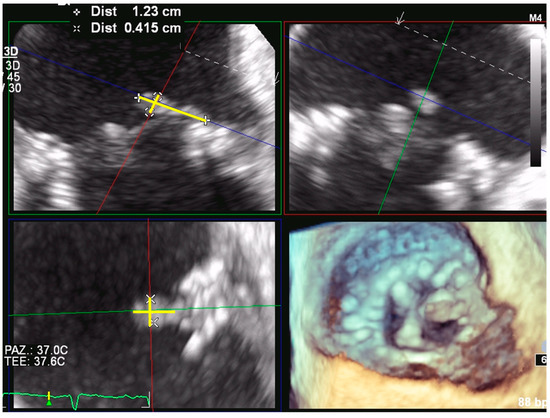

3.1. Mitral Paravalvular Leak